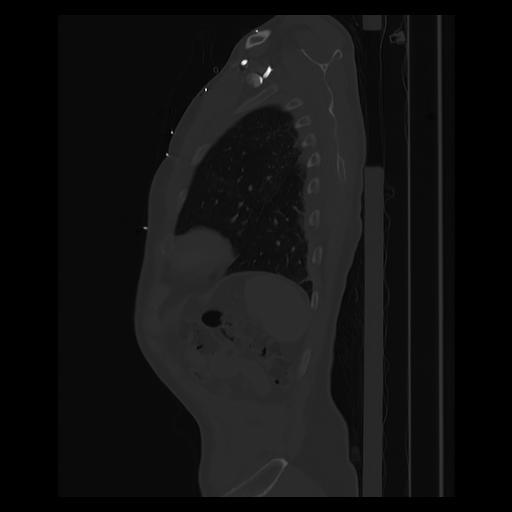

33 PULMON,CE,Sagittal,3.000,PULMON,Sagittal,